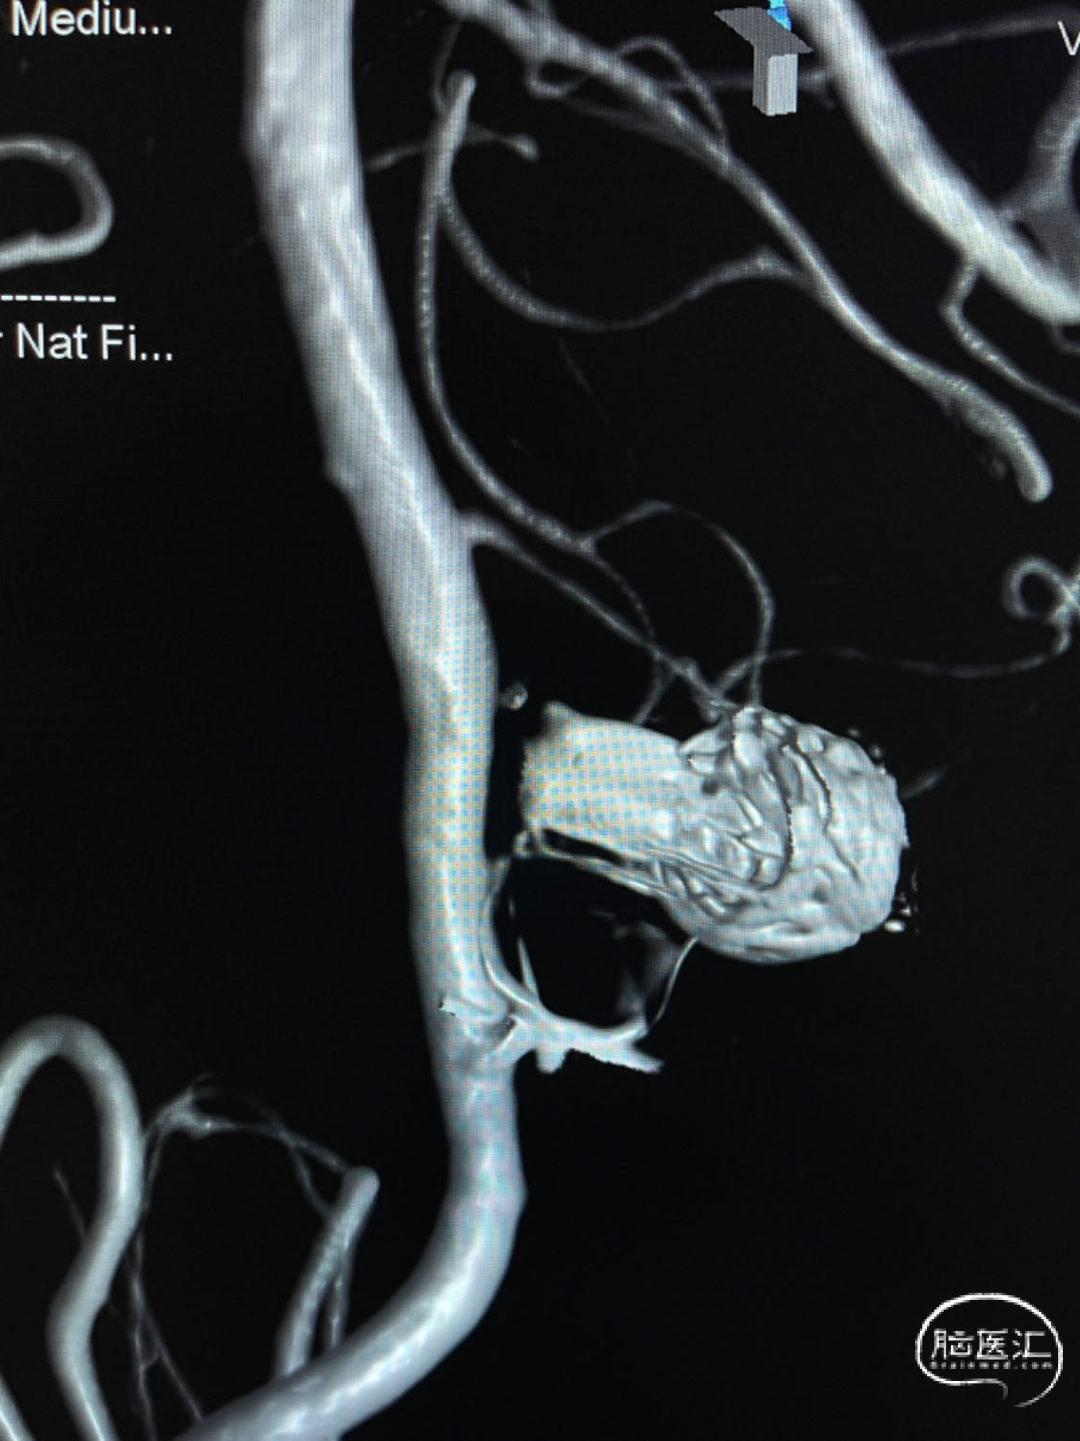

动脉瘤一:基底动脉末端动脉瘤,由左侧大脑后动脉与左侧小脑上动脉瘤夹角处动脉瘤形成且为不规则状;瘤体上有子囊形成,左侧小脑上动脉从近心端瘤颈处动脉瘤瘤体上发出,动脉瘤与载瘤动脉近直角。

经测量可得动脉瘤宽度平均值为8.88mm,动脉瘤最小高度为7.71mm,瘤颈约为4.03mm。参考尺寸选择表,选择WEB™ SL 10*5,VIA™ 33微导管。

缓慢推出WEB™从种子至萌芽状态,继续向瘤腔内远端缓慢推送WEB™至萌芽至开花间状态;将WEB™和VIA™送至瘤顶,固定WEB™推送杆回撤VIA™,WEB™完全释放。

经造影可见WEB™尺寸合适,贴合瘤壁,小脑上动脉分支,大脑后动脉分支等血流通畅。解脱后,再次造影和Dyna-CT评估,可见动脉瘤瘤腔内有明显造影剂滞留,小脑上动脉瘤显影良好,分支血管血流正常。